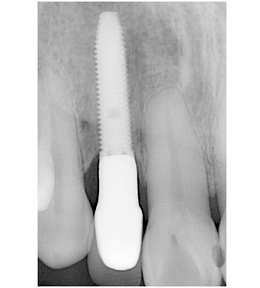

前歯部・審美領域の抜歯即時インプラント

右上の歯の前から2番目を抜歯し、即時にインプラントを施した前歯部・審美領域の治療

-

- 主訴

- 右上2の被せ物が取れた

- 治療内容

- 被せ物が脱離した右上2は歯根破折をしており、保存不可能と判断されたため抜歯と同時のインプラント埋入を計画。抜歯と同時にインプラント埋入。そのインプラントの生着を待って上部構造の装着を行なった

- 治療費用

- 435,000円(税別)

- 治療期間

- 3ヶ月